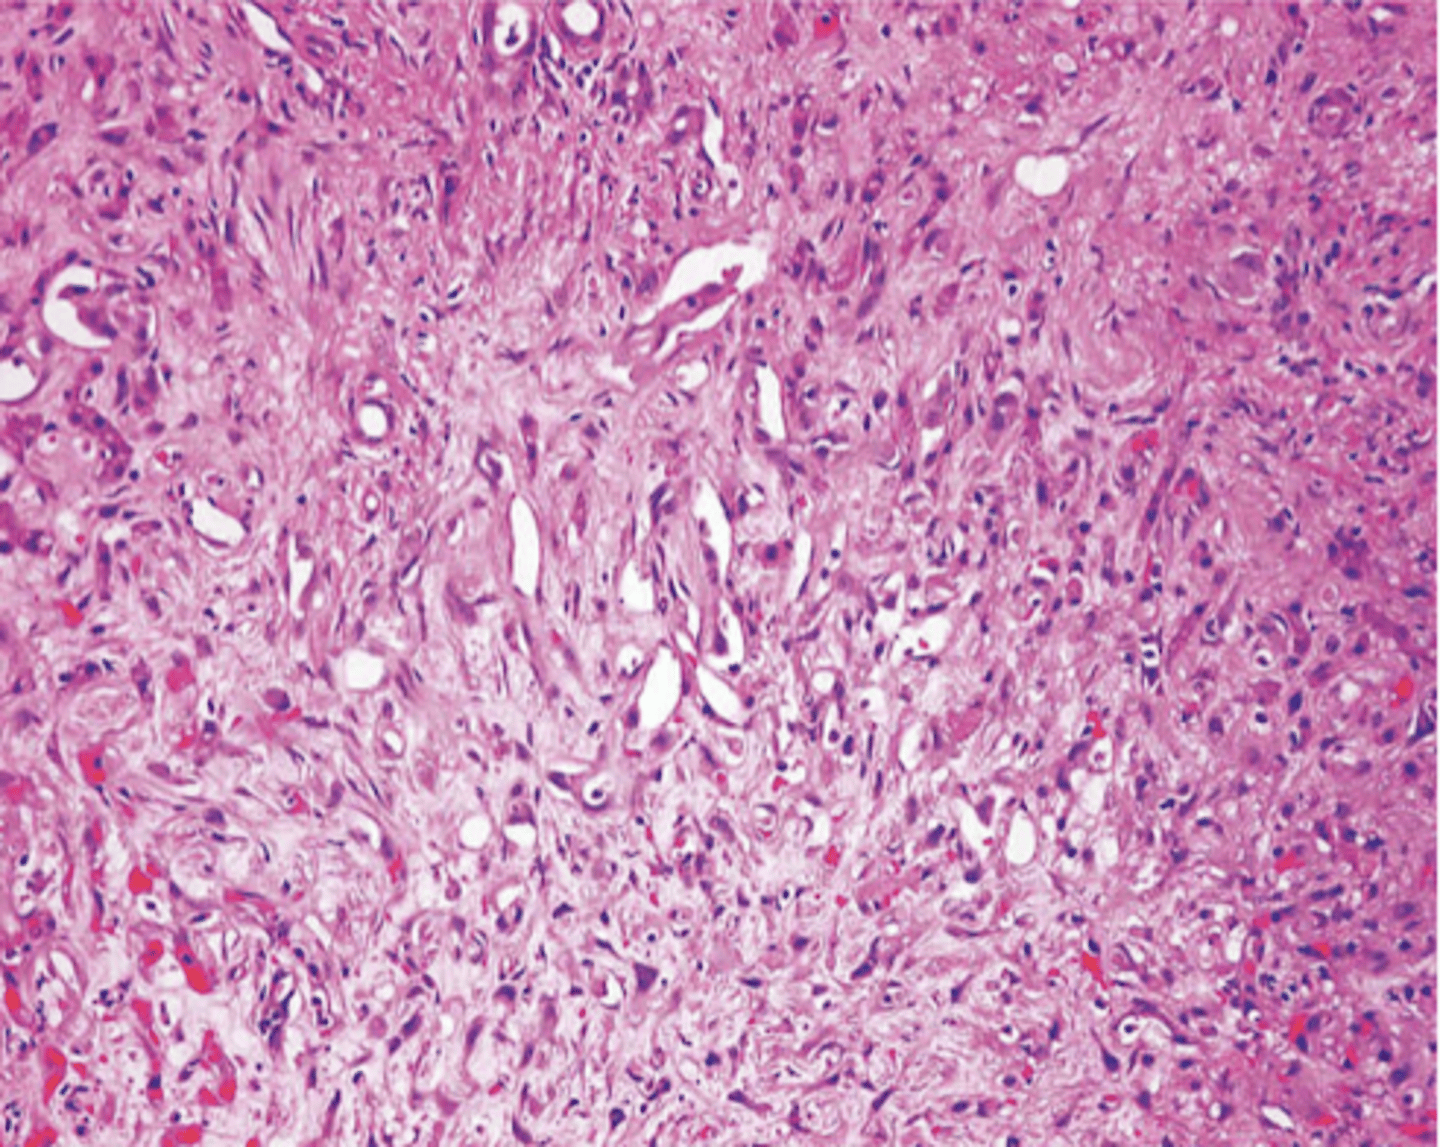

angiosarcoma

malignant endothelial neoplasm

appearance of angiosarcoma

starts as small papule

progresses to large, fleshy red tan to gray white lesions with blurred margins, necrosis, hemorrhage

CD31 (vWF)

endothelial origin

angiosarcoma